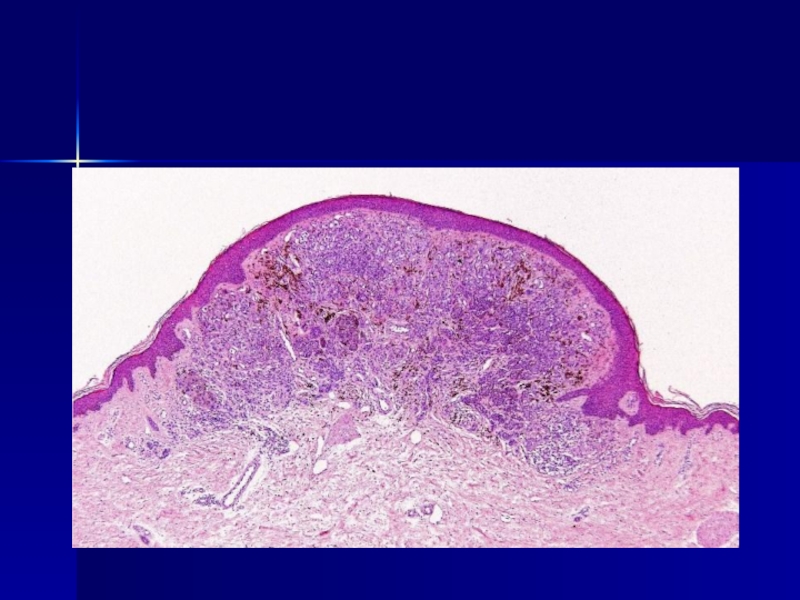

Слайд 12Невус Шпитц

Невус Шпитц

Слайд 13Невус Шпитц (ювенильный невус)

Невус Шпитц (ювенильный невус)